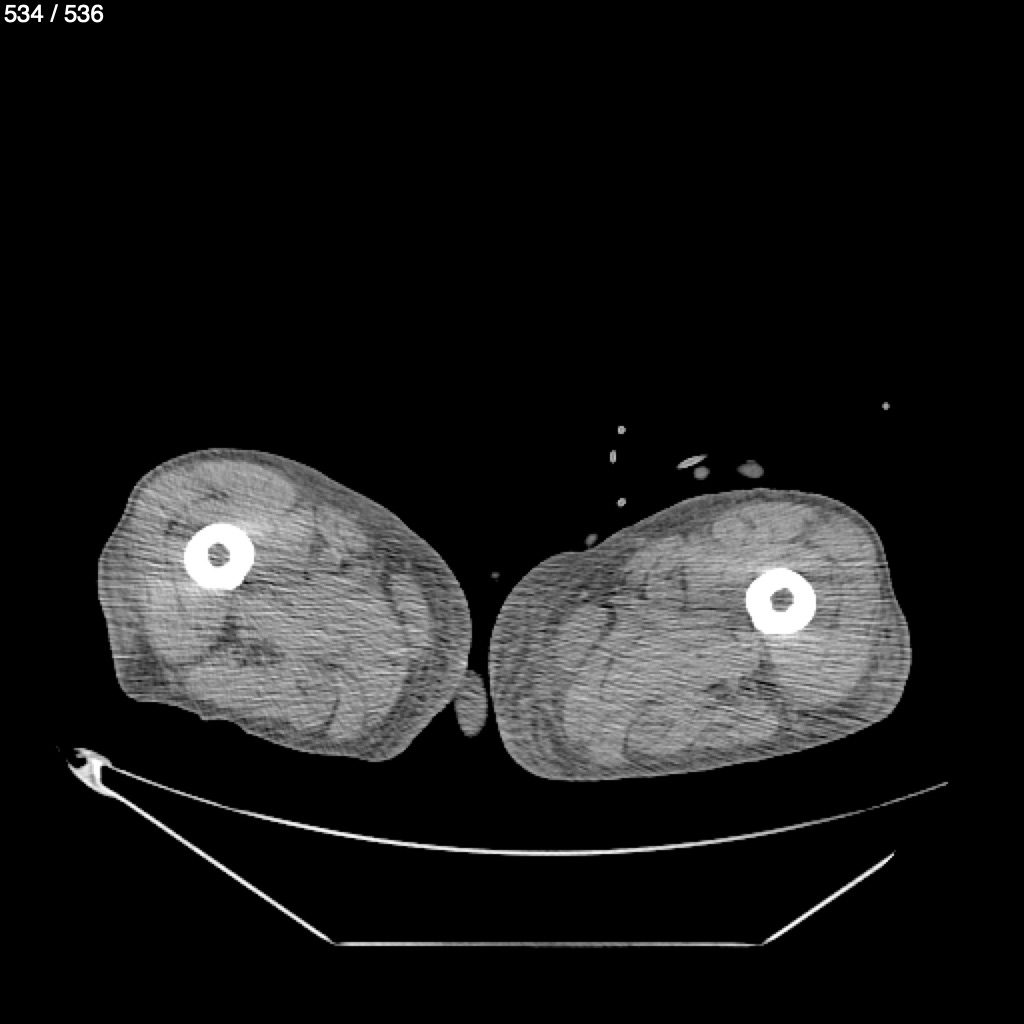

Angel Villalobos Palomeque 73 A - T.C Abdomen Simple